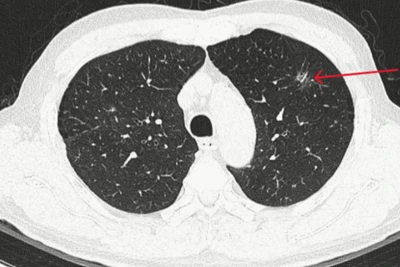

Những người thuộc nhóm nguy cơ cao cần khám lọc để phát hiện sớm, điều trị kịp thời và quản lý bệnh COPD hiệu quả. Ảnh: THẾ ANH